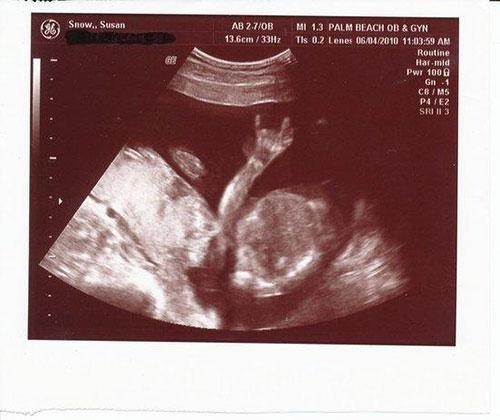

Bebeklerinin bu ilk görüntüsüyle anne-babalar şoke oldu!

El işareti yapan bebek